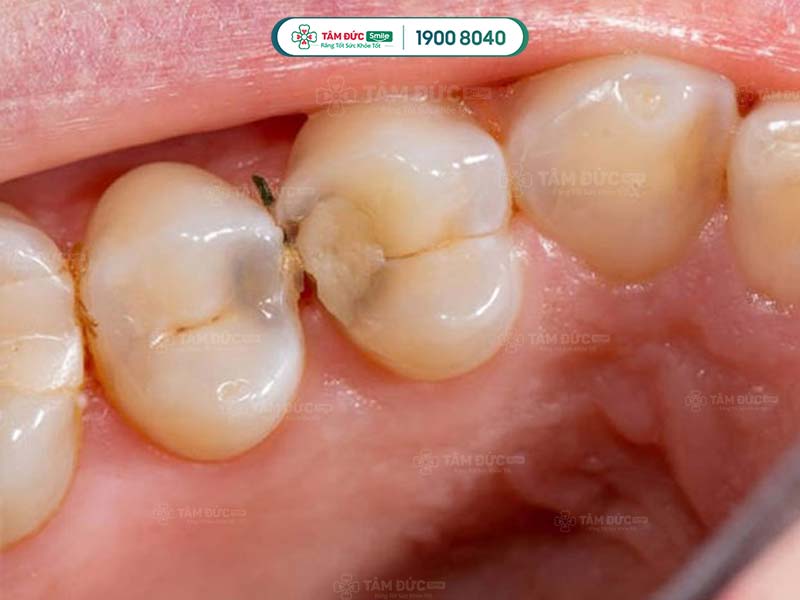

Sâu răng là nguyên nhân chính làm kẽ răng hàm bị đen hoặc làm cho răng bị đổi màu. Sâu răng do vi khuẩn tấn công, phá hủy men răng và ngà răng. Chúng tiết ra axit làm mòn mô cứng, tạo ra các lỗ nhỏ trên răng. Theo thời gian, các lỗ nhỏ này dần phát triển thành lỗ đen mà Quý khách có thể nhìn thấy bằng mắt thường.

Trong đó, sâu răng chủ yếu xảy ra ở rìa răng và kẽ hở giữa các răng. Đây cũng là nguyên nhân phổ biến làm kẽ răng bị đen, gây mất thẩm mỹ.

Kẽ răng hàm bị đen do nhiều nguyên nhân